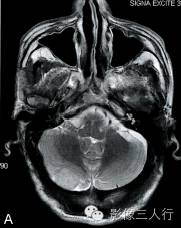

A.T2WI横断面;B.T1WI横断面;C、D、E.增强横断面、矢状面、冠状面;F.HE×100

图A、B:平扫MRI显示右侧小脑后缘类圆形结节状病灶,大小约1.4cm×2.0cm×1.8cm,在T2WI呈稍高信号,T1WI为稍低信号,边界清楚,信号均匀,局部脑组织受压内移。图C~E:Gd-DTPA增强扫描显示结节呈较均匀明显强化,病灶边缘清楚,其中在横轴位图像显示肿瘤中央部分强化较周围明显,且类似日光放射状。矢状位、冠状位图像见肿块强化变均匀一致,紧贴小脑后方硬脑膜或颅骨,但未见明显硬脑膜尾征。